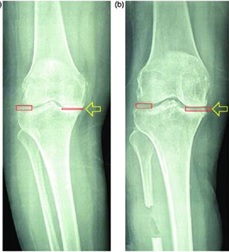

Подобно высокой остеотомии большеберцовой кости проксимальная корригирующая остеотомия малоберцовой кости может облегчить симптомы медиального остеоартроза с перестройкой нижней конечности. Однако, хотя исправление оси конечности является основной целью высокой остеотомии большеберцовой кости, принцип проксимальной корригирующей остеотомии малоберцовой кости исходит из теории «неравномерного распределения».

Как следствие поддержки малоберцовой костью, «неравномерный» означает, что давление на плато большеберцовой кости является асимметричным, причем давление на медиальном плато более выражено, чем на латеральном плато. В конце концов, медиальное плато становится значительно ниже латерального, и в нижней конечности возникает варусная деформация. Эти изменения механической оси приводят к концентрации напряжений в медиальном компартменте и дегенерации хряща и мениска, которые являются основными патологическими проявлениями медиального остеоартроза. Таким образом, при «неравномерном распределении большеберцовой кости» медиальный остеоартроз можно также назвать «синдромом дисбаланса в коленном суставе».

Проксимальная корригирующая остеотомия малоберцовой кости ослабляет боковую поддержку малоберцовой кости и приводит к коррекции варусной деформации, которая впоследствии может смещать направление нагрузки от медиального отдела в сторону латерального отдела, что приводит к уменьшению боли и удовлетворительному функциональному восстановлению.